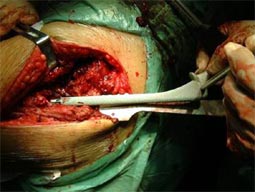

手术示意图:切除股骨头,磨平髋臼,新髋臼植入臼窝,

新假体的柄插入股骨,柄上安装新股骨头。假体柄可嵌入或骨水泥固定